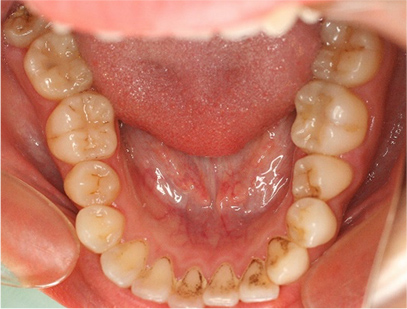

• 上側

• 下側